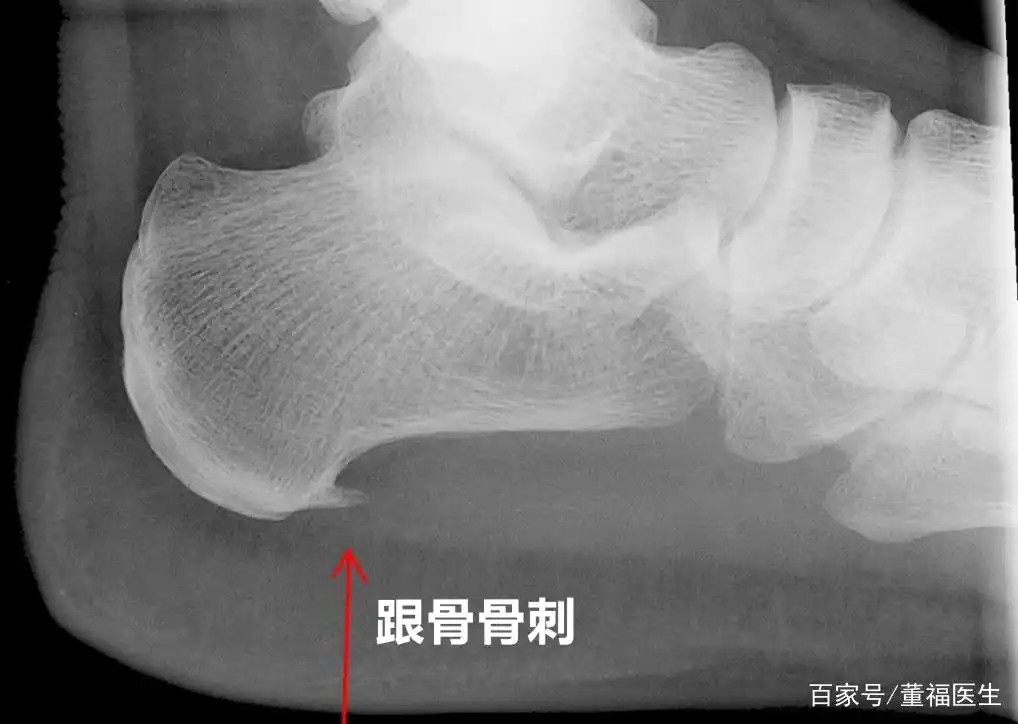

足跟痛是由跟骨骨刺引起的吗?真正的原因是什么?医生告诉您答案